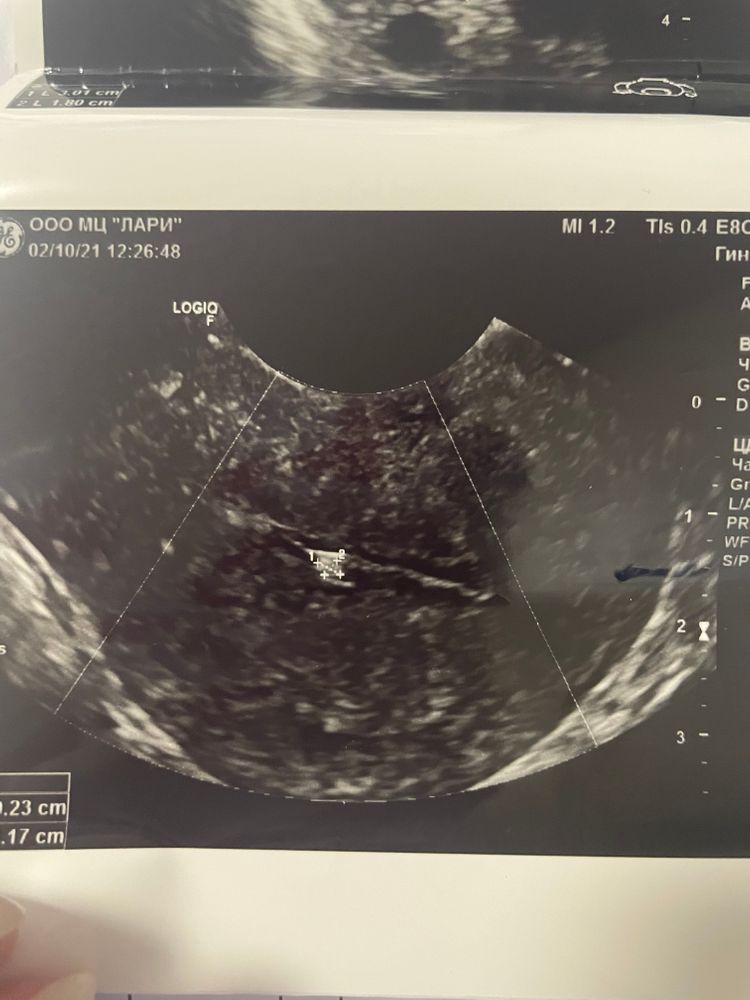

Девочки всем привет 🌺 история такая , в августе неудачное эко, в прошлом цикле ходила на фолликуломерию , на 8 дц, врач заметила «вроде полип?» 2мм ..

прошёл цикл , на 5 дц пошла на узи, другая клиника , врач говорит да есть что то но больше похоже на рубец , линия смыкания ровная на беременность не должно влиять , говорит не спеши на чистку .. не знаю что делать? 😞